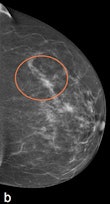

| Example of a subtle finding in a right-sided mediolateral oblique view, which was only reported by radiologists when using premium view (PV). A: Digitized prior. B: Tissue equalization (TE) processed image. C: PV processed image with the annotation. D: The resulting image of subtracting TE from PV. E: Thresholded version of D. White areas indicate that pixels in the PV image have relatively higher intensity than the related pixels in the TE image, whereas black areas indicate the opposite. In PV images, low-frequency trends are suppressed (no noticeable signal decrease in the breast edge in PV compared with TE), whereas higher-frequency structures are emphasized (e.g., glandular structures). All images courtesy of Wouter Veldkamp, PhD, Leiden University Medical Center. |

The local contrast optimization, premium view, has been designed to improve the quality of the information presented to the radiologist for diagnosis and also the reading speed by optimizing the local contrast in breast structures. In premium view, low-frequency structures are obtained from the original image by low-pass filtering. High-frequency structures are obtained by subtracting the low-pass filtered image from the original image. The low- and high-frequency images are both processed and weighted individually, then added together. The resulting image exhibits reduced contrast between different tissue types but enhanced contrast of small-scale anatomical architecture.

Another example of a finding in a left-sided craniocaudal view that was reported clearly more often by radiologists when using premium view (PV). A: Tissue equalization (TE) processed image. B: PV processed image with the annotation. C: Similar to image above, the resulting image of subtracting TE from PV. D: The thresholded version of C.For all six radiologists, perceived case suspiciousness -- defined as the highest probability of malignancy of all radiologist findings -- was higher using premium view optimization.

The major difference between the processing algorithms was an additional local contrast optimization when premium view was applied. "Premium view is aimed at increasing the visibility and suspiciousness of malignant lesions, but in our study the perceived suspiciousness of benign lesions and normal cases is increased as well," the researchers wrote. "An effect of local contrast enhancement could be that both normal (dense) structures and abnormal structures appear more suspicious due to their enhanced signal."